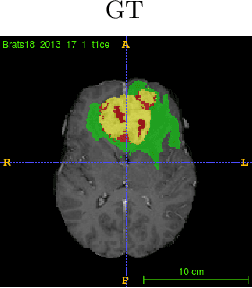

Abstract:In this work, we develop an attention convolutional neural network (CNN) to segment brain tumors from Magnetic Resonance Images (MRI). Further, we predict the survival rate using various machine learning methods. We adopt a 3D UNet architecture and integrate channel and spatial attention with the decoder network to perform segmentation. For survival prediction, we extract some novel radiomic features based on geometry, location, the shape of the segmented tumor and combine them with clinical information to estimate the survival duration for each patient. We also perform extensive experiments to show the effect of each feature for overall survival (OS) prediction. The experimental results infer that radiomic features such as histogram, location, and shape of the necrosis region and clinical features like age are the most critical parameters to estimate the OS.

Abstract:Segmentation of brain tumor from magnetic resonance imaging (MRI) is a vital process to improve diagnosis, treatment planning and to study the difference between subjects with tumor and healthy subjects. In this paper, we exploit a convolutional neural network (CNN) with hypercolumn technique to segment tumor from healthy brain tissue. Hypercolumn is the concatenation of a set of vectors which form by extracting convolutional features from multiple layers. Proposed model integrates batch normalization (BN) approach with hypercolumn. BN layers help to alleviate the internal covariate shift during stochastic gradient descent (SGD) training by zero-mean and unit variance of each mini-batch. Survival Prediction is done by first extracting features(Geometric, Fractal, and Histogram) from the segmented brain tumor data. Then, the number of days of overall survival is predicted by implementing regression on the extracted features using an artificial neural network (ANN). Our model achieves a mean dice score of 89.78%, 82.53% and 76.54% for the whole tumor, tumor core and enhancing tumor respectively in segmentation task and 67.90% in overall survival prediction task with the validation set of BraTS 2018 challenge. It obtains a mean dice accuracy of 87.315%, 77.04% and 70.22% for the whole tumor, tumor core and enhancing tumor respectively in the segmentation task and a 46.80% in overall survival prediction task in the BraTS 2018 test data set.